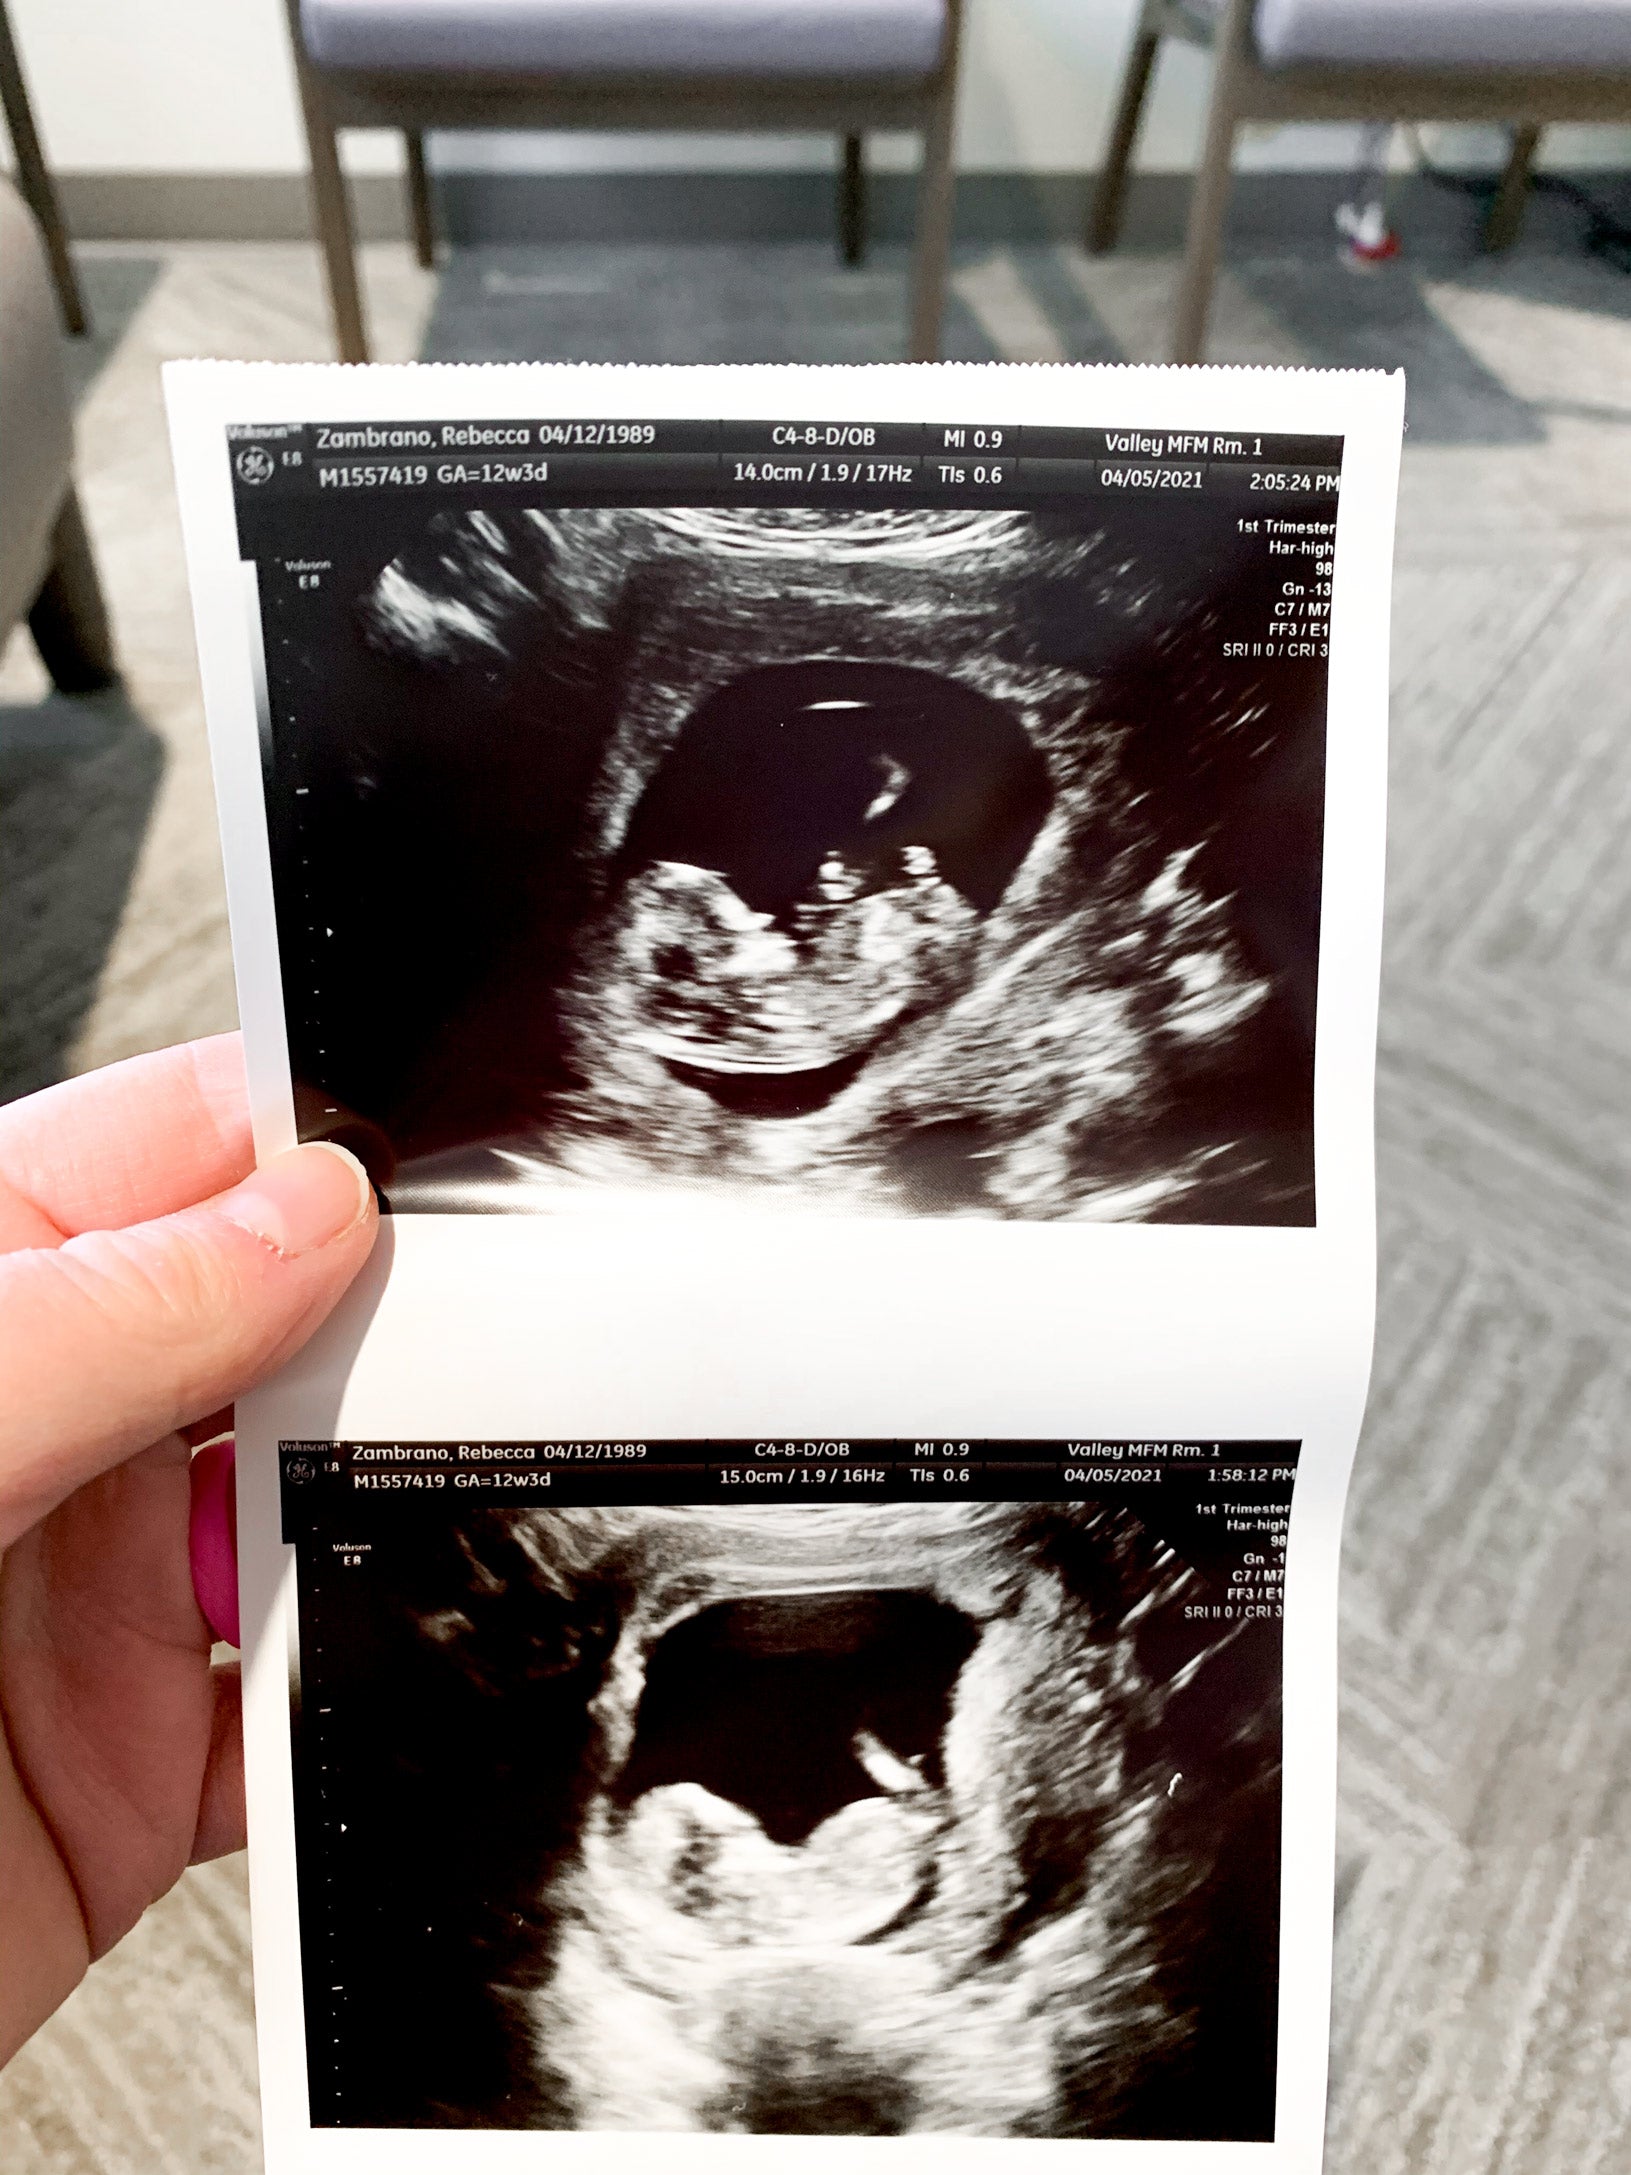

Here’s to Mosie being our literal life-giving savior! It was such a positive, pleasant experience for us both not having to worry or plan that time every other day to have sex and it feeling like a chore no one really wanted to do. It brought a different connection between my husband and we can’t thank you enough!! I’m now 12 weeks pregnant and just had my NUCHAL scan and everything is looking great! Baby Z was moving around like crazy and had a strong heartbeat!